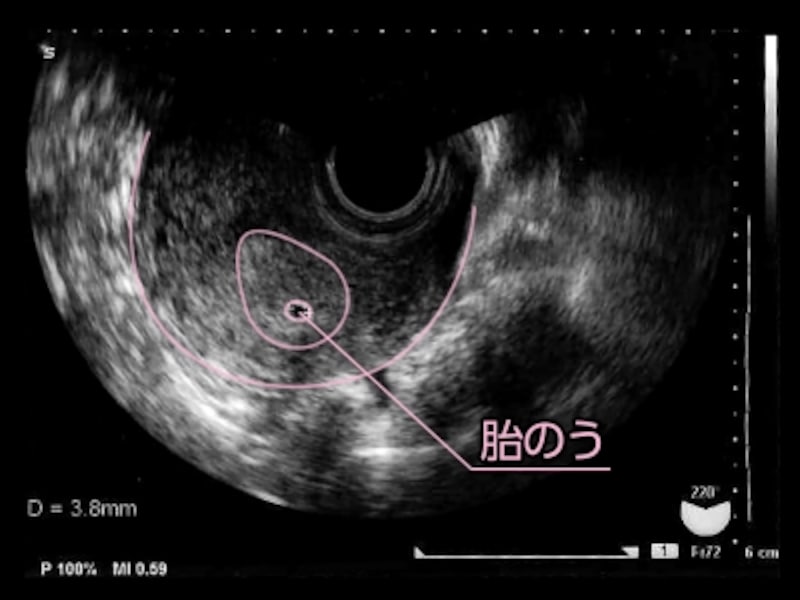

妊娠初期の胎嚢の大きさの目安はどれくらい エコー写真あり ママズアップ

妊娠初期の胎嚢の大きさの目安はどれくらい エコー写真あり ママズアップ

医療監修 胎嚢 たいのう とは 確認方法や確認できる時期を知ろう ママリ

5 産科一般超音波検査 初期編 正常所見4 7週 日本産婦人科医会